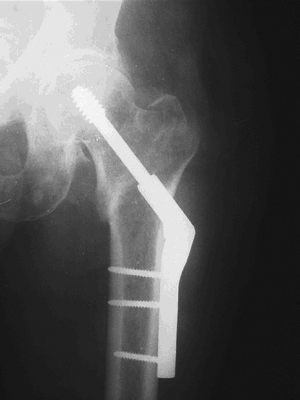

This is the most commonly used device for

both stable and unstable fracture patterns. It is available in plate

angles from 130 to 150 degrees (Fig. 30.4).

Figure 30.4. X-ray of a sliding hip screw.(From Bucholz RW, Heckman JD, Court-Brown C, et al., eds. Rockwood and Green’s Fractures in Adults, 6th ed. Philadelphia: Lippincott Williams & Wilkins, 2006.) -